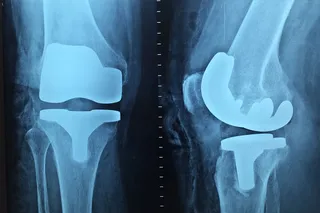

"As age advances, the bones become brittle as calcium reduces in the body leading to bone deformities, stress fractures and affecting the day-to-day life of women. It can be taken care of with extra supplementation apart from a nutritional and dietary intake of calcium available in our daily sources of vegetables and non-veg foods," said Dr. Komal Chavan, who coordinated the mega-camps.